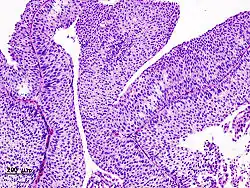

The 1973 WHO grading system for transitional cell carcinomas (papilloma, G1, G2 or G3) is most commonly used despite being superseded by the 2004 WHO[14] grading for papillary types (papillary neoplasm of low malignant potential [PNLMP], low grade, and high grade papillary carcinoma). High-grade carcinoma typically displays more pleomorphism, multiple mitoses, euchromatin and relatively prominent nucleoli, and uneven distribution of nuclei.

Transitional cell carcinoma, being low-grade to the left, and high-grade to the right. H&E stain -

- ^ Image is taken from following source, with some modification by Mikael Häggström, MD:

- Schallenberg S, Plage H, Hofbauer S, Furlano K, Weinberger S, Bruch PG; et al. (2023). "Altered p53/p16 expression is linked to urothelial carcinoma progression but largely unrelated to prognosis in muscle-invasive tumors". Acta Oncol. 62 (12): 1–10. doi:10.1080/0284186X.2023.2277344. PMID 37938166.{{cite journal}}: CS1 maint: multiple names: authors list (link) - ^ Source for role in distinguishing PUNLMP from low-grade carcinoma: